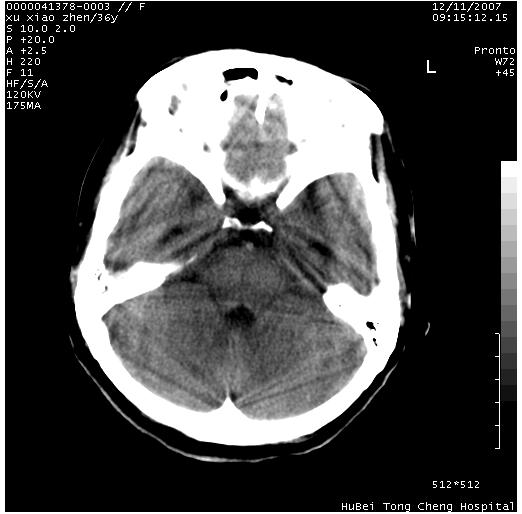

以下是引用wzr在2007-12-12 18:58:00的发言:[br]以脑白质受累,脑肿胀明显,脑室变窄,多考虑炎性改变,建议进一步ce或mri明确.

以下是引用wqs571018在2007-12-12 19:48:00的发言:[br]脑白质受累,脑肿胀明显,脑室变窄,多考虑炎性改变,脑膜炎可能性大;建议mri明确.。